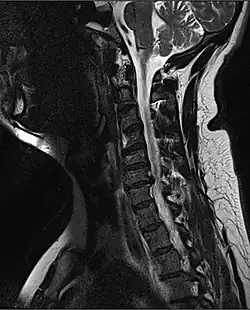

![]() | |

| MRI of a fractured and dislocated cervical vertebra (C4) in the neck that is compressing the spinal cord | |